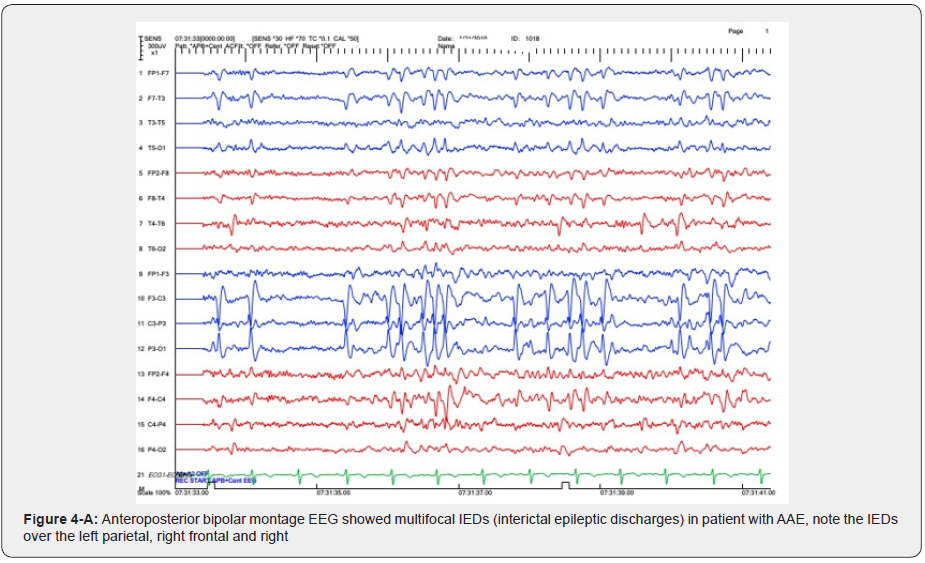

In the majority of JS background activity is normal for the patient’s age but in three (30%) is slower than normal for age. All of these patients had intellectual disabilities. This finding is similar to other studies [3] (Figure 4A, 4B). Focal interictal spikes in JAE patients is common (50%) and frontocentral predominant SWD also is common in the CAE patients (Focal and generalized SWD) [14]. one of the most interesting points in our study is a case of CAE with ictal focal onset from right posterior which according to our knowledge has not reported so. In this patient’s epilepsy protocol, MRI was normal and there was not any focal abnormality in the right posterior regions (Figure 5,6). This issue should be observed carefully in future investigations about CAE. Clinically, AAE is often a component of Lennox–Gastaut syndrome associated with mental retardation and behavioral problems, for instance, inattention hyperactivity, aggressiveness, and autistic features [3]. in the present study we detected two patients with clinical and electrographic findings close to AAE without any intellectual disabilities and also, they had normal development and behavior. These patients had normal Brain MRI but focal IEDs were seen which was bifrontal in one and multifocal in another one. Both of them had a positive family history of epilepsy. It could be due to distinct genetic susceptibility in AAE patients. This issue needs further investigations to report the AAE as a distinct epilepsy syndrome. In conclusion, JS or EMA–EM should be considered in refractory childhood absence epilepsy and video-EEG recording is a useful method if EMA-EM is suspected. Focal ictal onset could be recorded in generalized epilepsies which should be considered in future investigations. Pure Atypical Absence Epilepsy (AAE) without LGS could be added as a distinct epilepsy syndrome in the future.

Absence seizures, are characterized by frequent sudden discontinuation of activities, brief staring episodes, with loss of awareness and abrupt recovery are commonly seen in a few pediatric generalized epilepsy syndromes including childhood and juvenile absence epilepsies (CAE, JAE), and juvenile myoclonic epilepsy (JME), absence with eyelid myoclonias (EMA–EM or Jeavons syndrome), epilepsy with myoclonic-atonic seizures (Doose Syndrome) and Lenox-Gastaut Syndrome (LGS). The EEG feature in CAE and JAE patients usually demonstrates generalized Spike-Wave Discharges (SWD) averaging 3HZ frequency with the normal background. This type of absence seizure respond to specific antiepileptic drugs including ethosuximide and valproic acid, however some patients with absence seizures may having drug-resistant epilepsy by International League Against Epilepsy (ILAE) definition [1]. failure rate is about 53% and 58% for ethosuximide and valproic acid, after 16 weeks of therapy [2]. Atypical Absence Seizures (AAS) have slower SWD on EEG (1.5-2.5 HZ), Interictal Epileptic Discharges (IEDs) usually have multifocal epileptiform features. This type of seizure begins before 5 years of age and sometimes associated with diminished postural tone, tonic, or myoclonic activity. AAS often diagnosed as a component of LGS [3]. Eyelid myoclonia with or without absences (EMA-EM) is recognized as a seizure type by the International League Against Epilepsy (ILAE). Idiopathic EMA-EM (or JS) has been described as a long-lasting condition beginning in childhood and having a higher incidence in girls [4,5]. The EEG presentation of JS has been described as focal occipital or frontal predominant SWD in both interictal and ictal stages [6,7].